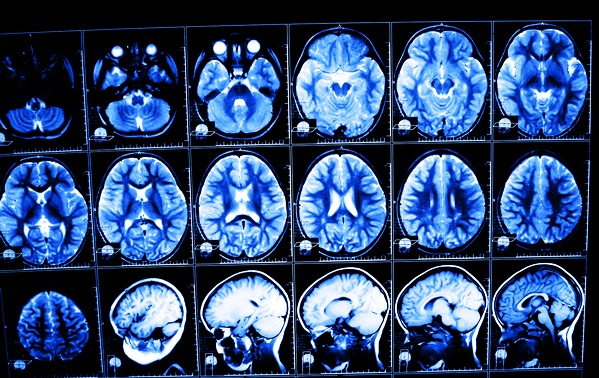

Выраженность симптомов, их продолжительность, сроки восстановления от последствий ЧМТ во многом будут зависеть от тяжести повреждения черепа и мозговых структур непосредственно во время получения травмы и при ее начальном лечении. Многие неврологи отмечают, что наш мозг является крайне пластичной структурой, отличающейся высокой гибкостью, которая может в полной мере восстановиться даже после сильных повреждений. Сразу после поступления пострадавшего в больницу проводится МРТ, УЗИ, КТ и другие необходимые обследования, чтобы установить тяжесть полученной травмы в соответствии с общепринятой классификацией и обнаружить поврежденные структуры мозга.

Если медикаментозные средства, традиционные процедуры не помогают устранить болевой синдром, пациента отправляют на повторную процедуру МРТ или КТ, чтобы выяснить, что именно становится причиной боли (нарушения в проходимости сосудов, скрытые кровоизлияния и гематомы, защемления нервов и т.п.). Если болевой синдром выраженный, существенно ухудшает качество жизни человека, то может быть показано проведение операции.